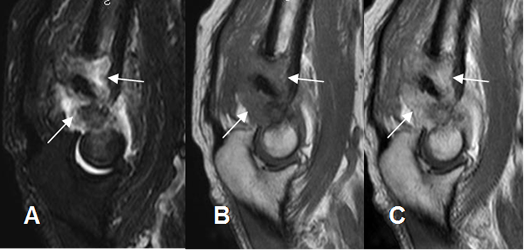

Fig 77. Osteocondroma.

A: Rx AP, B: RM coronal en T1 y C: RM sagital en T1. Exostosis del húmero con continuidad de la medular osea, por osteocondroma.